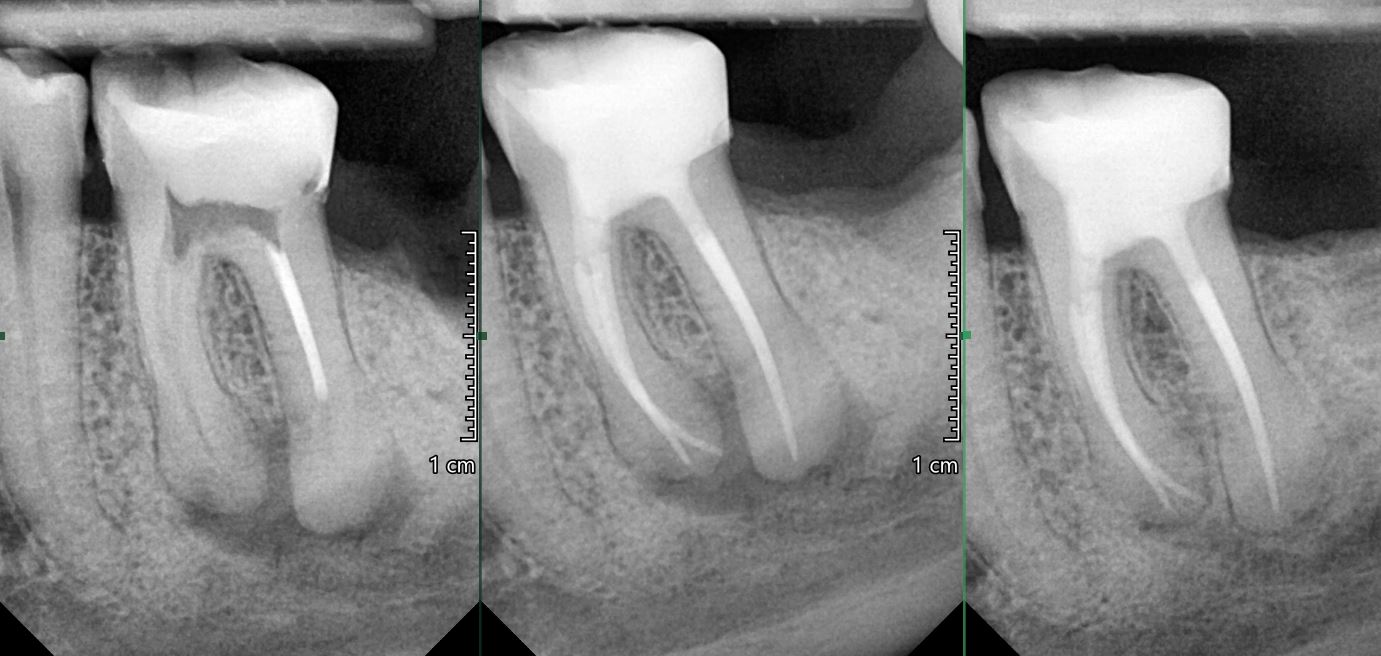

OŠETŘENÍ PACIENTŮ POD OPERAČNÍM MIKROSKOPEM

Nabízíme možnost delegovat Vaše pacienty k (re)endodontickému ošetření pod operačním mikroskopem.